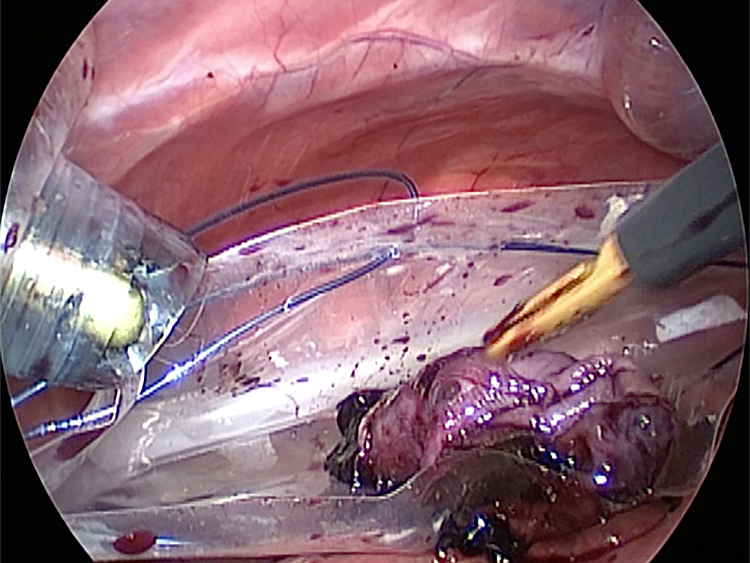

お腹にトロッカーを4本挿入し、そこから鉗子とカメラを入れて胆嚢を肝臓から剥がしていきます。 カメラで拡大しながら見ることができるので開腹手術よりも視野が確保できます。

手術の様子

胆嚢の周囲の脂肪や膵臓、十二指腸が激しく癒着し剥離が困難な状態でした。胆嚢は全く確認することができませんでした。

少しずつ癒着を剥がして胆嚢が確認できるようになってきました。 こんなに癒着していることはあまりないので過去に膵炎や胆嚢炎を起こし苦しい時期があったことが推測されました。 それにしてもなかなか胆嚢はでてきませんでした。